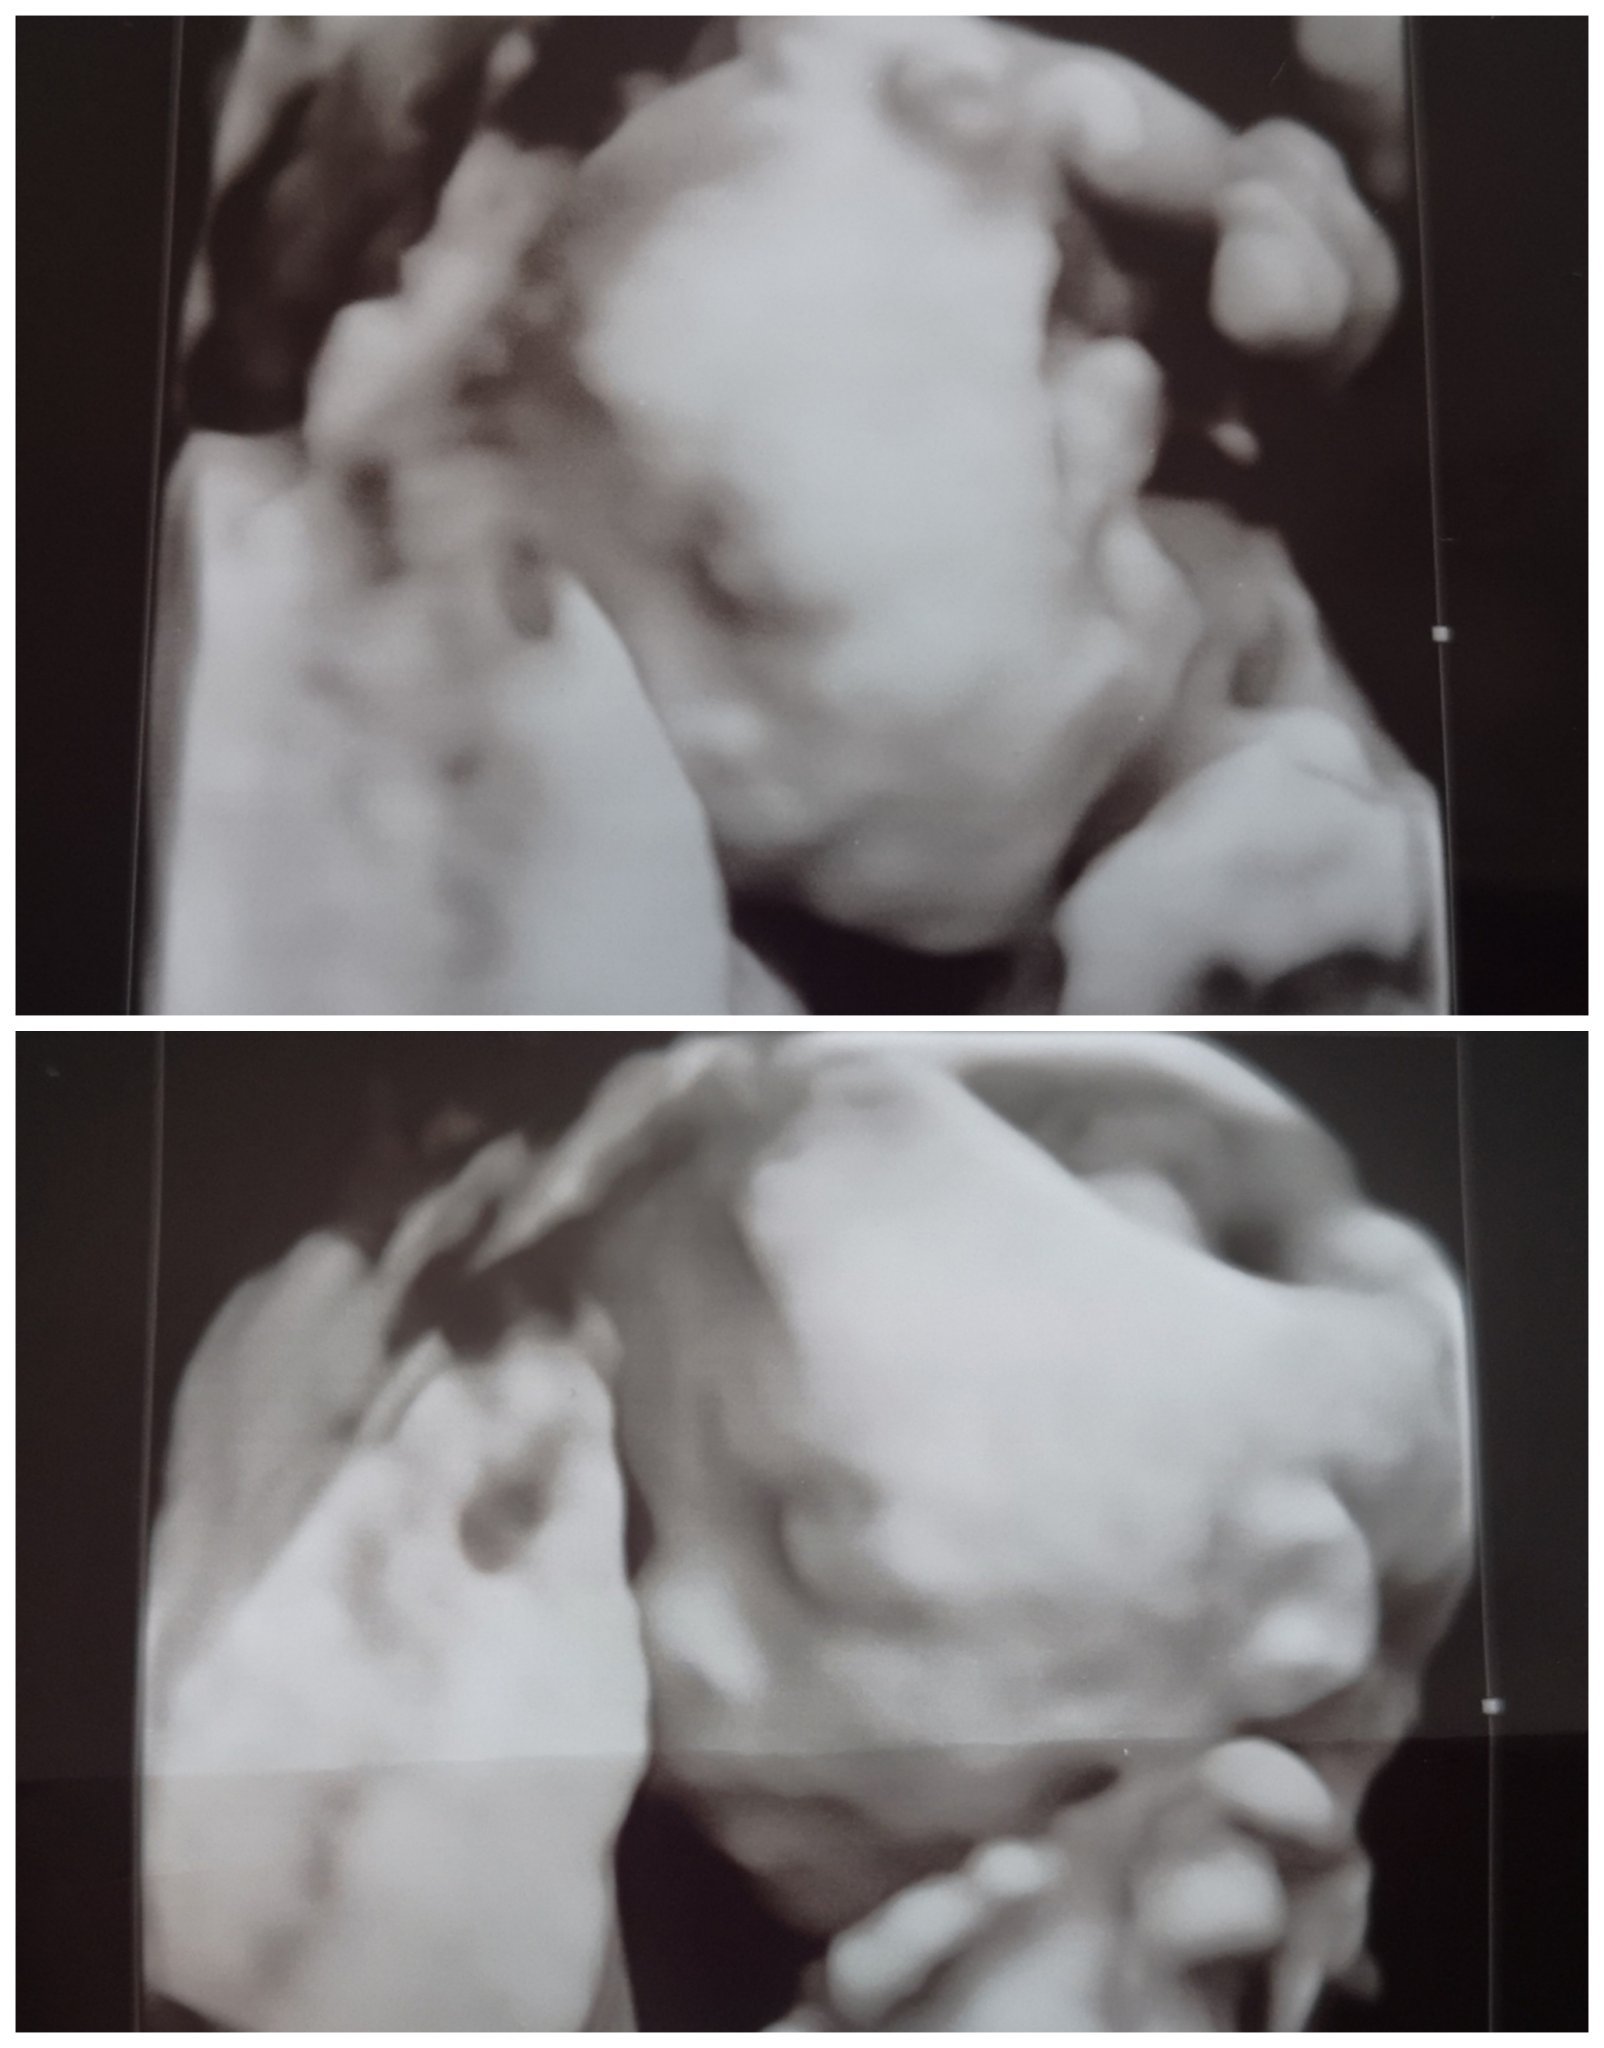

Аз да се похваля, че си имаме здрава госпожица, тежаща 300 гр. в 20-та седмица. ❤️ Прегледът беше емоционален... разплаках се, като я видях...първата ни среща 😊🥰

Габи, аз бях на втора фетална днес при лекарката, която ми води ЖК в Бургас. Доколкото разбрах от нея, предстои да ми даде и още снимки при следващите прегледи, ако малката ни позволи, разбира се. Не съм заплащала допълнително за снимките. ❤️